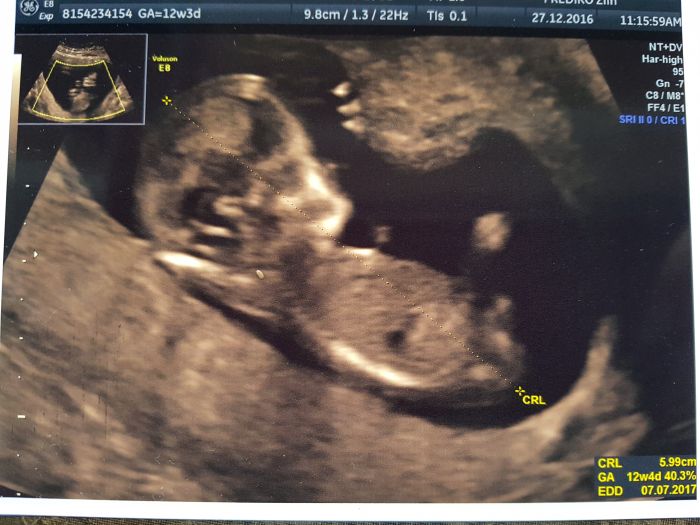

Tak ja mam za sebou uz kontrolni UTZ screening,min. utery, vsechno nastesti v poradku, vysetreni trvalo cca 15min. Dr. byl uzasny, vysvetloval a ukazoval uplne dopodrobna co a jak a kde je co. Nosni kustku, sijove projasneni, mozek, ocicka, nosik, usi, rucicky, zaludek, ledviny, poslouchali jsme srdicko, mocovy mechyr, nozicky. Byl to nadherny pocit. Slza mi i ukapla. Delal to pres brisko a muj a dcera sedeli hned vedle v sedacce a sledovali vsechno na velke obrazovce. Pri zeptani na pohlavi rekl ze tak na 70% to vidi na kluka ze se mu zda ze tam neco couha. Toho jsme si vsimli i my s mojim pri ukazovani kde je mocovy mechyr. Taky jsem to videla. Ale rikal ze to neni jeste 100% ze mi to rekne az v tom 20tt na 100%.

Rikal mi rizika DS a jeste dalsich nemoci tak to mam 1:6500 a 1:50 000. Rikal ze jsou to skvele vysledky i kdyz uz jsem v zacatcich rizikove hranice 35let. Poucil me ze muzu jit na dalsi testy, odber plodove vody, samozdrejne ze je to moje volba, rikal mi riziko pri odberu plodovky potratu. Ale ze podle skvelych vysledku nevidi duvod. Samozdrejme ze mi nezarucuje 100% garanci zdraveho miminka. Zitra jdu jeste k mojemu dr tak si to jeste jednou necham poradne vysvetlit tu zpravu od nej.

Dostala jsem 2 fotecky prilozim pozdeji. A podle Utz TP 7.7. hezke datum?